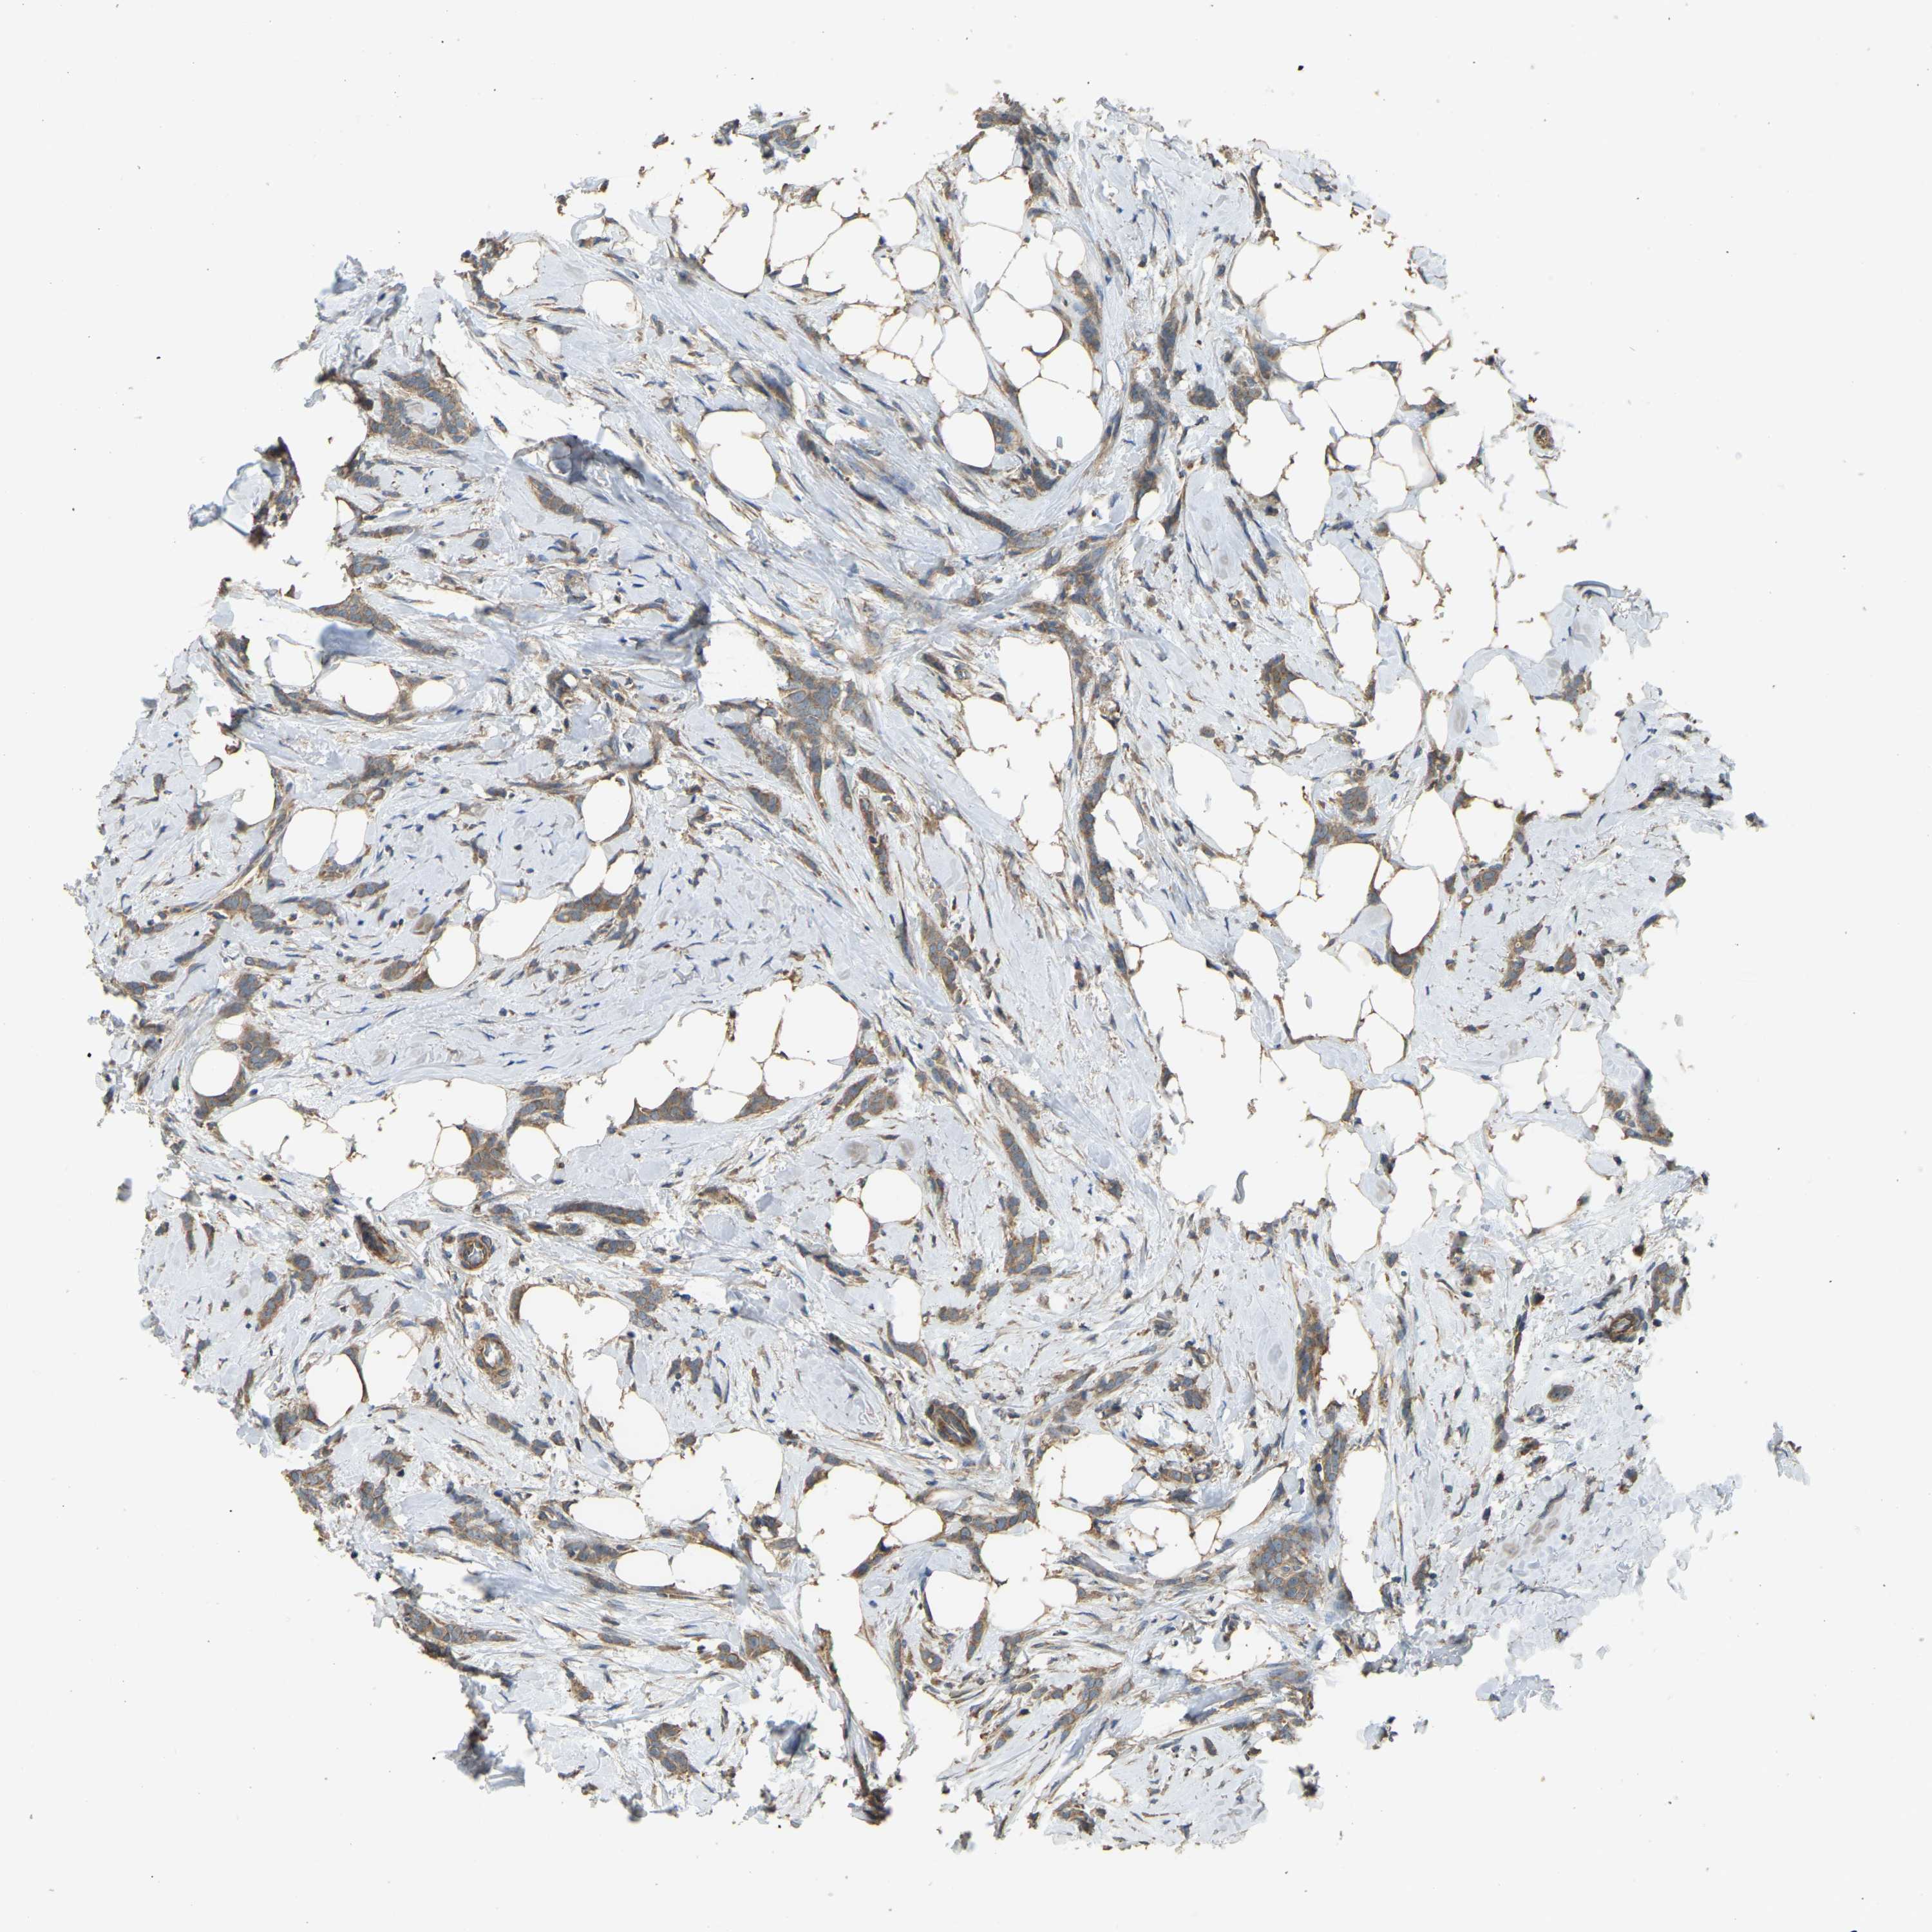

Breast cancer

Human cancer